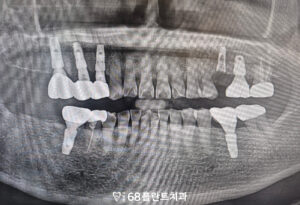

위 환자분은

식사를 할 때 마다 치아가

전체적으로 아프고 불편하다며

광명시치과 이편한68플란트에

내원해 주셨습니다.

확인해 보니,

이미 치아가 상실된 부위가 있었고

여러 치아에는 크랙이 발생해

저작 시 통증과 불편함이

반복되고 있는 상태였습니다.

균열의 진행 정도가 심해

보존이 어려운 치아들은

발치를 결정하였으며,

기존에 치아가 상실된 부위와 함께

임플란트 식립을 진행하기로 계획하였습니다.

먼저 임플란트를 위해

치아를 발치하고

잇몸뼈가 부족한 부위에는

뼈이식을 함께 하여

임플란트 식립을 진행하였습니다.

임플란트 식립 후

초기 고정이 중요하기 때문에

환자분께 주의사항을 충분히 안내드리며

안정적인 회복이

이루어질 수 있도록 도와드렸습니다.

이후 임플란트가 잇몸뼈에 잘 결합되어

정밀한 보철 작업을 통해

자연스러운 형태와 저작 기능을

회복할 수 있도록

치료를 마무리하였습니다.